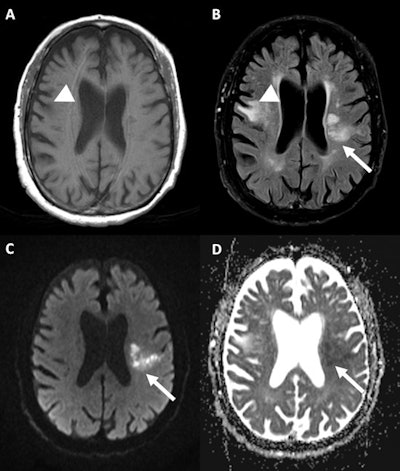

A 77-year-old male patient was found unconscious in a state of dehydration and hyperthermia. MRI shows old right frontal cortico-subcortical infarction (arrowhead) on T1-weighted (A) and T2-weighted imaging (B), with new acute posterior left frontal subcortical infarct (arrow) confirmed on diffusion-weighted imaging (C) and apparent diffusion coefficient map (D) sequences. Images courtesy of Dr. Camilo Pineda Ibarra et al. and presented at ECR 2023.The authors decided to analyze the MRI characteristics of CNS involvement in heatstroke. They studied the brain MRI scans of patients diagnosed with heatstroke at Hospital Clínic de Barcelona between April 2010 and September 2022. They presented their findings in a poster at ECR 2023.